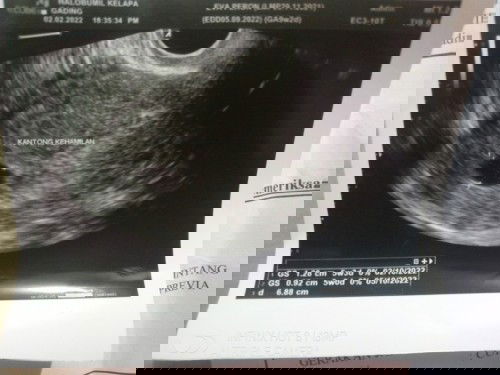

Halo bunda,aku mau tanya dong.pengalaman yg pernah Bo dan next kehamilan nya berhasil kram hamil.mudanya sampe usia.minggu kbrapa yah..agak.kuatir krn riwayat Bo yg pertama.yg kdua sampe usia 8 minggu msh suka kram dikit.dan aku msh kantong janin.blm ada baby nya..thank you yg mau jawab. #Trimester1 #RiwayatBo #kramperutbagianbawah #KramHamilMuda #seriusnanya #bantusharing